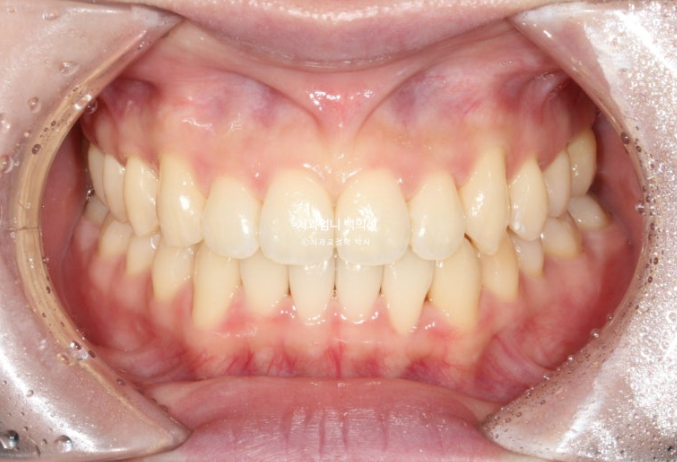

25.04

중심선과 교합이 좋고 기울어진 앞니 하나의 치축도 개선이 되었습니다.

아무리 인빚러라인이라도 교합이 좋지 않으면 치료를 마무리 짓지 않습니다.

이제 전후비교 해보겠습니다.